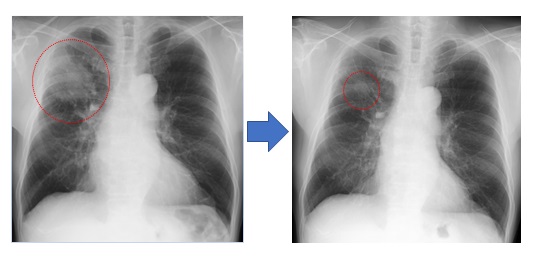

将来の肺がん治療成績の向上を目指した臨床試験や治験にも積極的に取り組んでおり、特に最新の分子標的薬を用いた治療も行っております(図6)。

図6. 1次治療が無効であったステージIVの進行肺腺癌に対して(左図)、2次治療として免疫チェックポイント阻害剤のペムブロリズマブ(抗PD-1抗体)の投与を開始し、6か月後には腫瘍が著明に縮小しました。(右図)